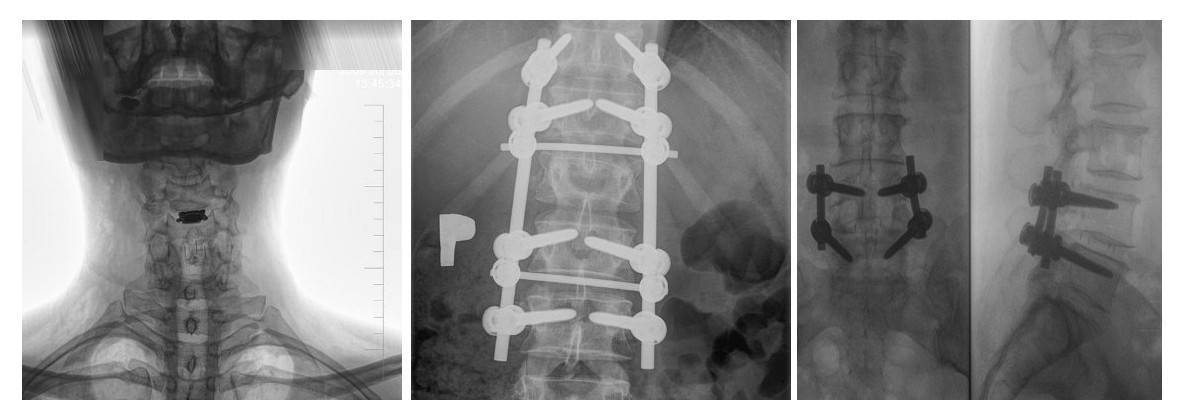

Do wykonywanych zabiegów w zakresie kręgosłupa należy zaliczyć też zabiegi resekcji trzonów i implantów trzonów kręgów w odcinku lędźwiowym kręgosłupa. Ponadto podejmuję się leczenia powikłań osteoporozy kręgosłupa. Moja oferta to również stabilizacja tylna, międzywyrostkowa w dyskopatii lędźwiowej i zespole po nukleotomii.

- stabilizacje transpedicularne i implanty międzytrzonowe PLIF Plivios ,

- stabilizacja kręgosłupa lędźwiowo-krzyżowo-biodrowa,

- stabilizacja transpedicularna przy złamaniu kręgosłupa lędźwiowego,

- stabilizacja kręgosłupa z wykorzystaniem śrub kaniulowanych,

- stabilizacja złącza piersiowo-lędźwiowego,